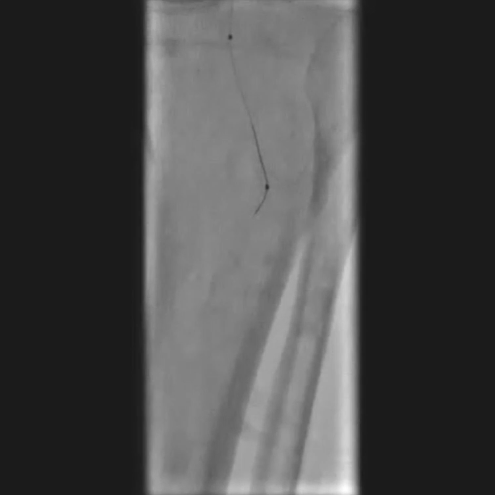

先尝试顺行穿刺,导丝进入内膜下未能成功通过;改为逆行穿刺胫后动脉,导入V18导丝,采用Safari技术(逆行导丝通过闭塞段与近端导管对接)建立工作轨道。